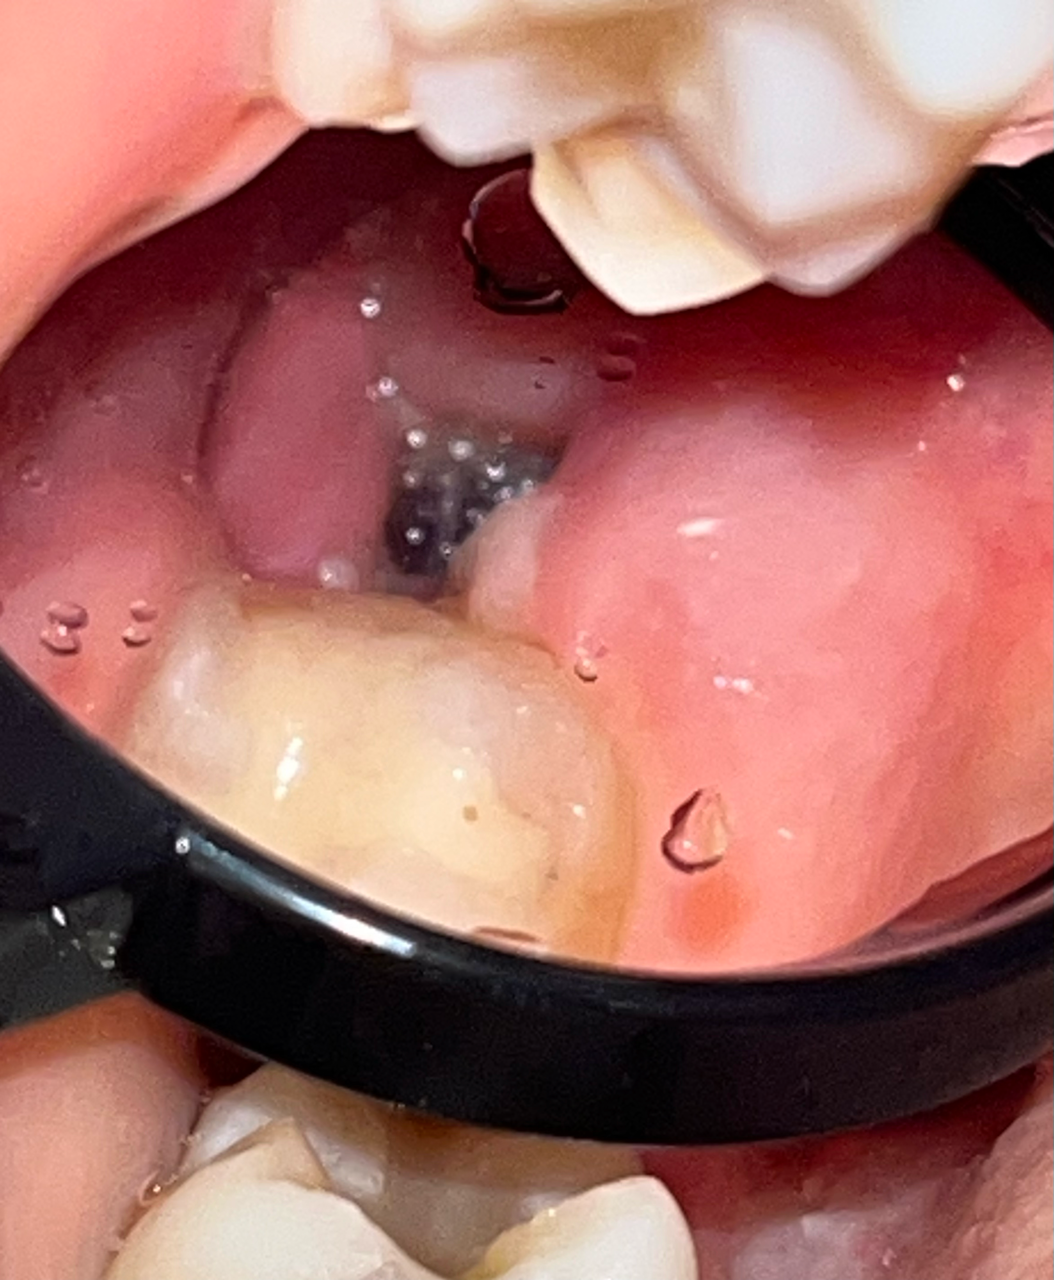

Здравствуйте, сегодня третий день после удаления верхнего зуба мудрости, удаление простое, без швов, зуб не ретинированный. Подскажите, пожалуйста, нормально ли проходит заживление и не похоже ли внешне на сухую лунку? К сожалению, лучших фото сделать не удалось. Вчера после чистки зубов было немного кровавой слизи после легкой ванночки хлоргексамедом. Боль слабая, при разговоре и жевании, купируется обезболивающим. Антибиотик не был прописан, контрольного обследования тоже не были назначено. Ем я мягкую пищу и рот не полоскала активно. Спасибо большое заранее за ответ и хорошего дня!

На фото все нормально. Описание вашего состояние тоже соответствует норме. Если вы ожидаете развития альвеолита со стреляющими болям, то можно расслабится, т. к. на 4-ый день этого уже не произойдет.

"нормально ли проходит заживление" - Да, нормально.

"и не похоже ли внешне на сухую лунку? " - Нет, не похоже.